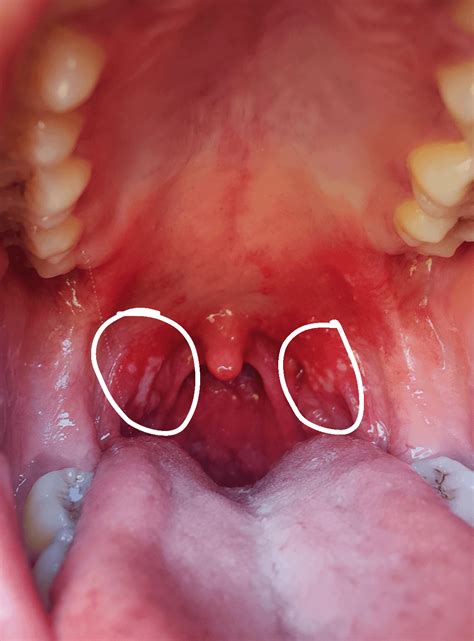

Discovering a whit spot on tonsil can be an alarming experience, often leading to immediate concerns about potential infections or other serious health issues. While the sight of these spots is certainly unsettling, they are usually a sign that your body is fighting off an infection or reacting to an accumulation of debris. Understanding the potential causes, symptoms, and when to seek professional medical advice is crucial for managing your oral health effectively. In this guide, we will explore the common reasons behind these spots, how they are typically treated, and when you should consult a healthcare provider.

There are several reasons why you might notice a white spot on your tonsils. Some causes are relatively benign, while others require medical intervention. It is important to differentiate between these conditions to determine the appropriate course of action.

• Tonsil Stones (Tonsilloliths): These are small, calcified deposits that form in the crevices of your tonsils. They are made up of bacteria, mucus, and food particles that become trapped and harden over time.

• Tonsillitis: This is an inflammation of the tonsils, usually caused by a viral or bacterial infection (such as Strep throat). It often results in white or yellow patches of pus on the tonsils.

• Oral Thrush (Candidiasis): A fungal infection caused by an overgrowth of Candida albicans. It often manifests as creamy white patches in the mouth and on the tonsils.

• Mononucleosis (Mono): Often called the “kissing disease,” this viral infection can cause severely swollen tonsils with a white or grey coating.

• Strep Throat: A bacterial infection that frequently causes severe sore throat, fever, and white, pus-filled spots on the tonsils.

It is often difficult to tell the difference between a harmless tonsil stone and a symptomatic infection just by looking at a whit spot on tonsil. However, paying attention to accompanying symptoms can provide significant clues.

Appearance Hard, yellowish or white, foul-smelling. Soft, creamy, or pus-like patches.